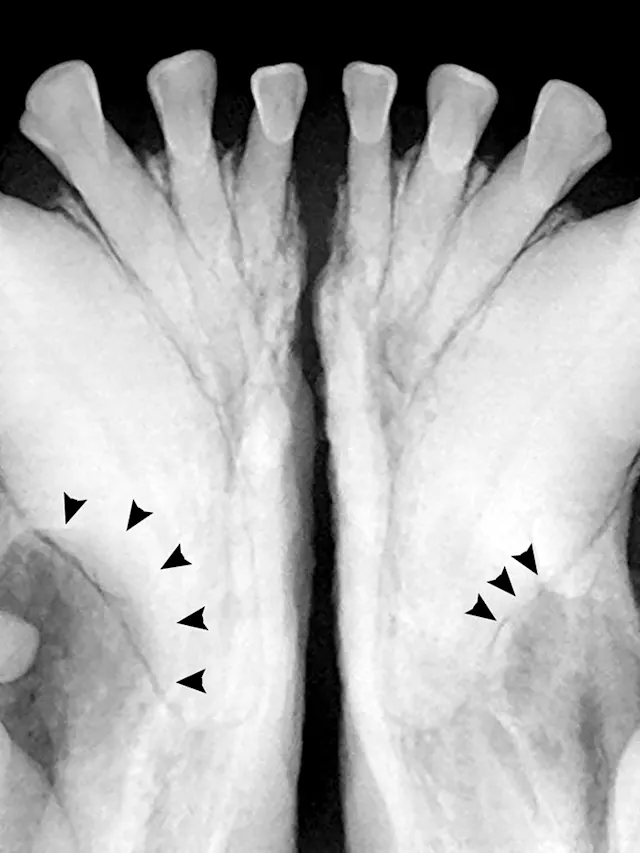

Full-mouth radiographs were obtained, with particular attention on the clinically missing mandibular premolars and the areas affected by gingival masses. Radiographs revealed unerupted mandibular 1st premolars situated in apparent cystic lesions, expansion of which resulted in involvement of the mandibular canines and 2nd premolar teeth. The apical portion of the mesial root of the mandibular premolar (306) was partially resorbed. Maxillary premolars were rotated bilaterally, but there were no periodontal consequences. Incidental findings included a supernumerary maxillary left first premolar 1 (205) and fusion of the roots of the left and right mandibular premolar 2 teeth (306 and 406). Horizontal alveolar bone loss was present at the area of 206, with radiolucency of the furcation area of 206 (Figures 3-6); the buccal aspect of 206 was covered by the gingival mass. Probing of the furcation was possible only from the palatal side and did not reveal furcation involvement.